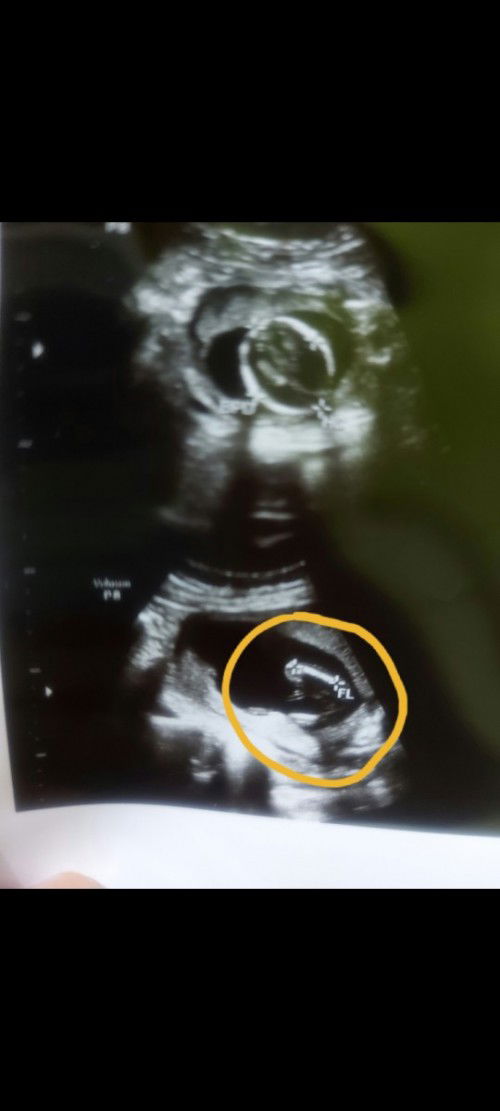

Mam ada yg pernah ngalamin gak? Setiap bulan USG ke klinik A ini hasil nya sama sama sesuai juga sama perkiraan bidan. Nah tadi aku di ajak temen USG ke tempat lain ke klinik B. Tapi kenapa hasil nya beda jauh bgt ya antara klinik A dan klink B. Yang tadi nya hpl 27 februari jadi pindah ke 25 maret.. jadi bingung saya mam.. yg mana yg bnr 🤔🤔#bantusharing

Đọc thêm